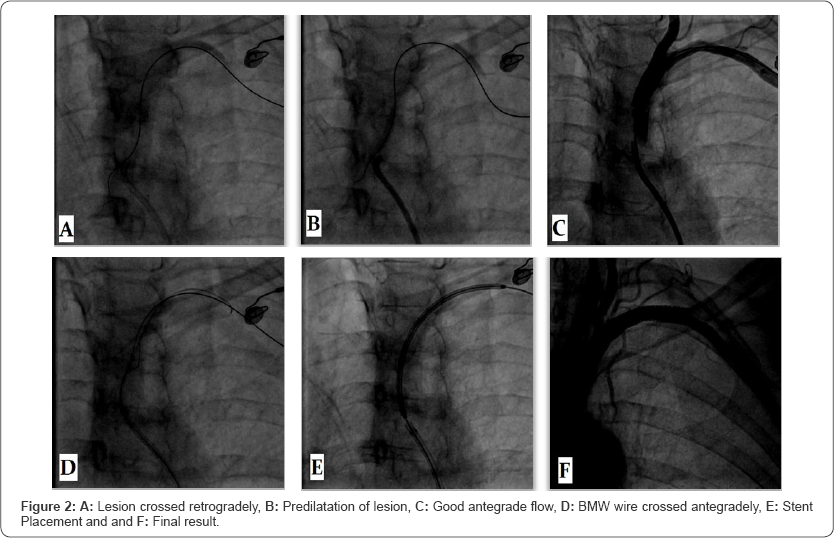

Ostia of left subclavian artery was engaged by using JR 7F guiding catheter. Check angio showed total occlusion. A 6F shuttle sheath was used to cannulate the vessel and placed distal to the occlusion. The lesion was crossed retrogradely using 0.014x190cm cross-it 200 and placed in proximal descending aorta (Figure 2A). Lesion was predilated using 3.5x15mm balloon at 8atm pressure (Figure 2B). Check angiogram through JR guiding catheter established good antegrade flow with no dissection (Figure 2C). Using another 0.014x180cm BMW wire crossed the lesion antegradely and the cross-it 200 wire removed (Figure 2D). An 8x32mm INVATEC scuba stent was deployed across ostio- proximal subclavian artery (Figure 2E) with a good angiographic result (Figure 2F).